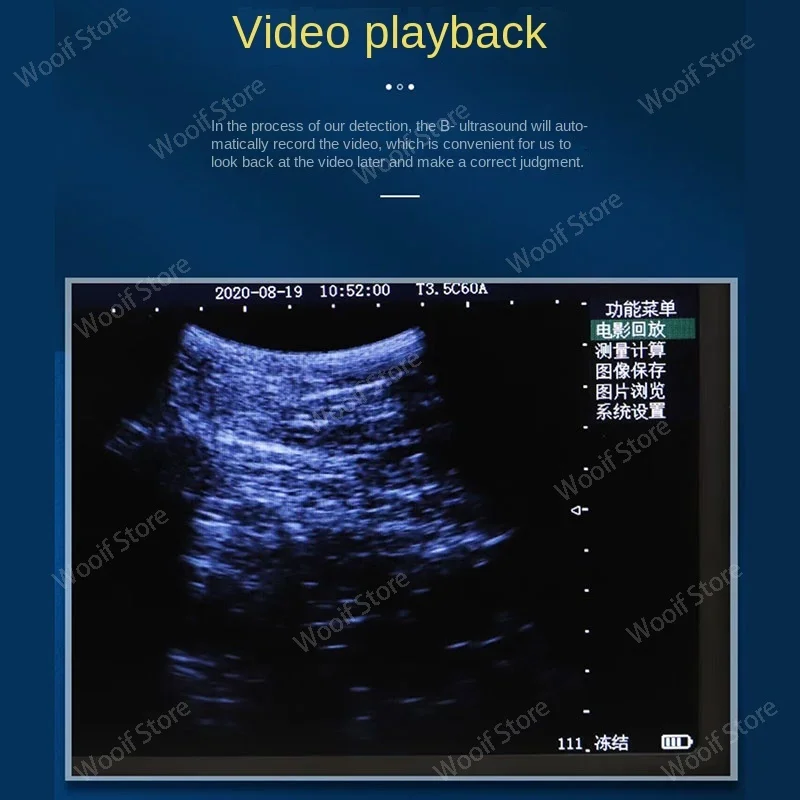

-Cineplay: auto and manual, frames can set as 100/200/500/1000

-Image save: jpg, avi and DICOM format

Linear Probe Pictures: